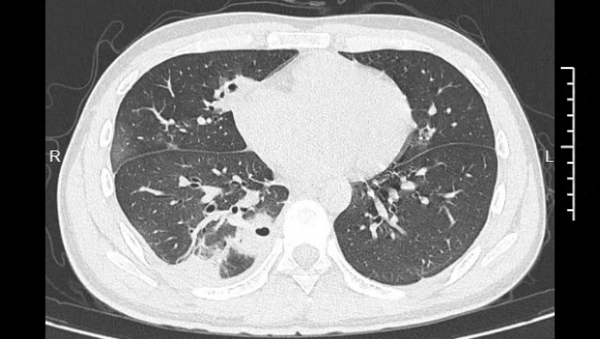

本以为挤完就完事了,结果没几天,高烧39度,胸口疼得像针扎一样。去医院一查,好家伙,医生都吓了一跳:小林的肺部CT图上,密密麻麻全是空洞,肺组织都坏死了! 医生确诊这是"血源性肺脓肿"。

小林的肺部CT影像显示多个空洞